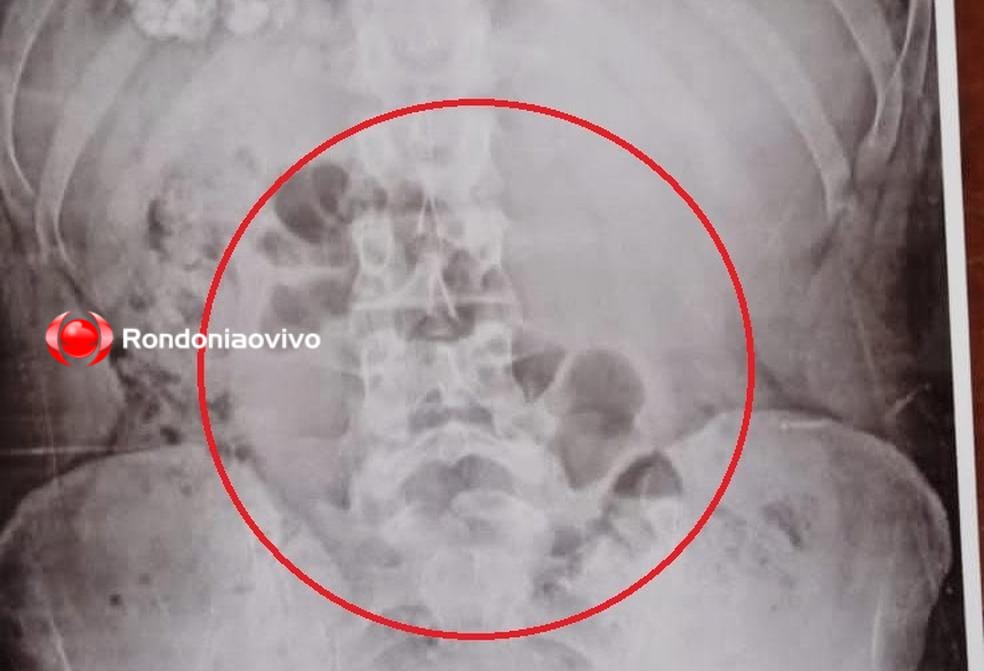

Atenção, o texto contém uma imagem que pode chocar os leitores mais sensíveis

Brasileiro que morreu em avião tinha 80 sacos de cocaína no estômago

Estrangeiros são presos irregularmente na BR 364; peruano levava 40 cápsulas com cocaína dentro do estômago